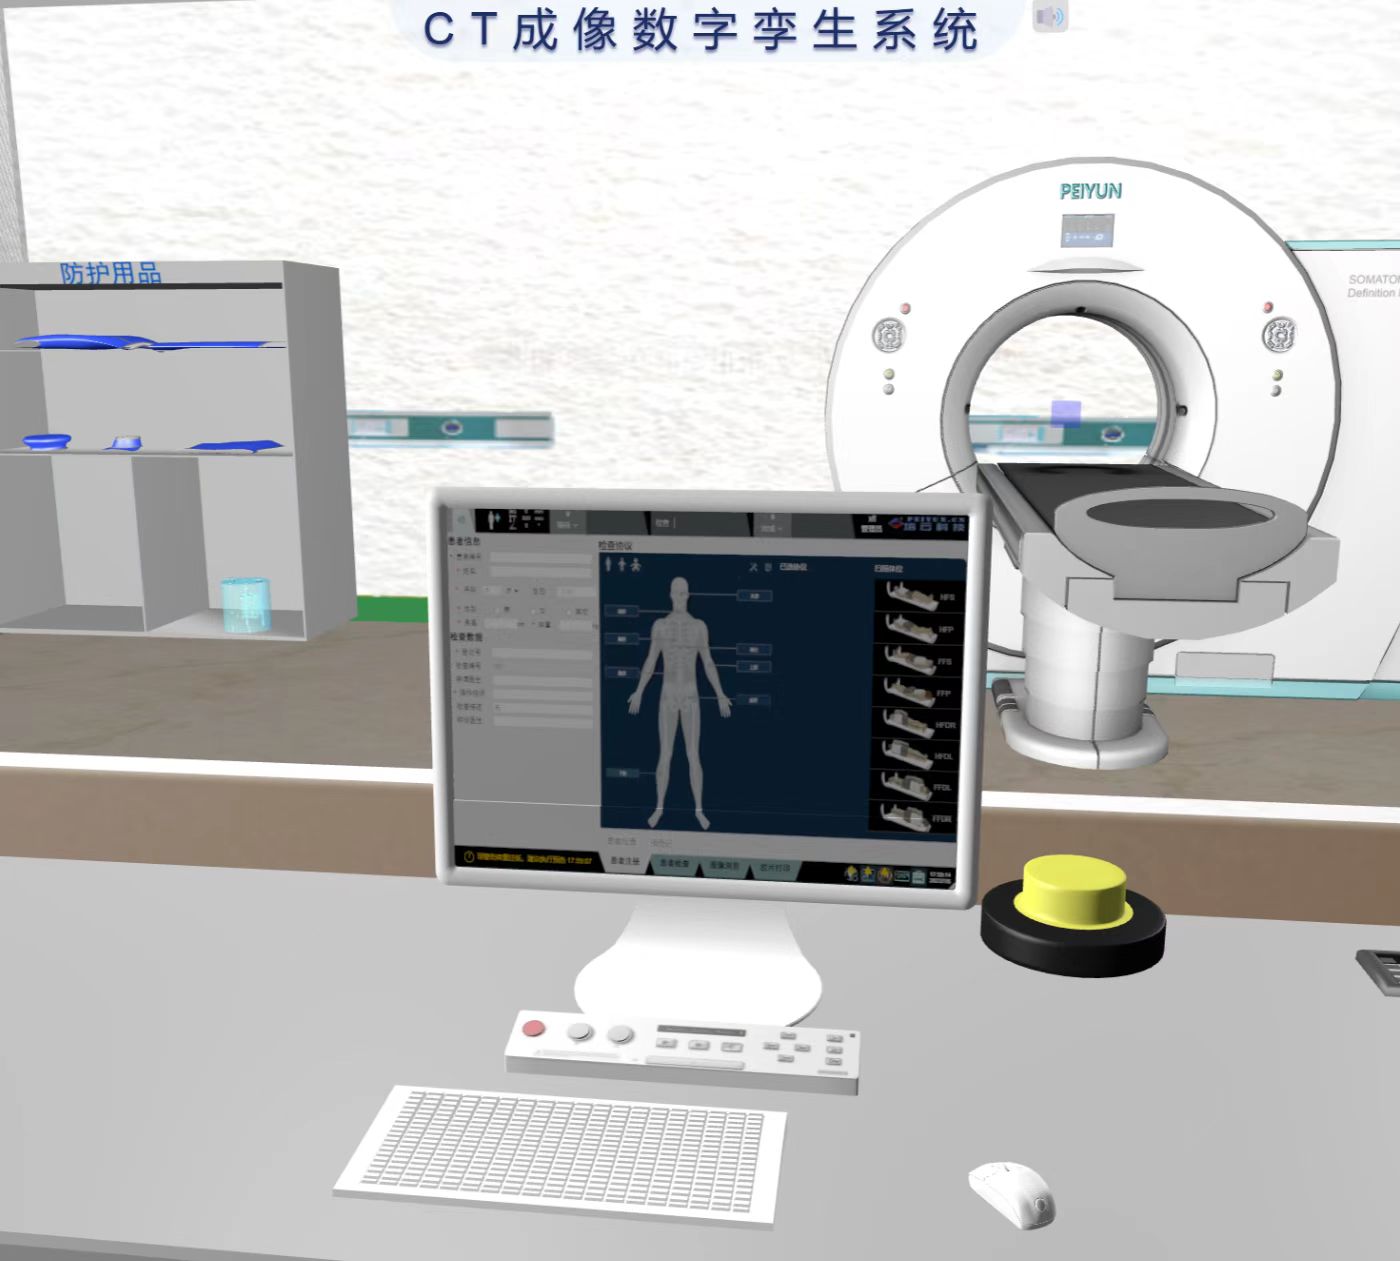

基于数字孪生技术构建的 MRI 检查技术模拟系统,实现了机理与场景的深度融合,操作逻辑与真实设备完全一致,打造高度逼真的虚拟检查环境。虚拟场景完整复现 MRI 检查全流程,从技师登录、叫号、查验检查单、引导患者更衣等事项,到线圈选择、摆位、序列与参数设置等环节均细致还原。

系统内置基于人体摆位和参数的标准数据库(数据源自临床规范与专家共识),可对操作全过程进行精准量化评分,确保实训考核的标准化。此外,系统支持模拟灯芯绒伪影、化学位移伪影、运动伪影等十余种常见伪影,并可针对不同伪影设置考核场景,要求操作者制定并执行相应处理方案,强化对影像质量控制能力的培养,助力医学影像技术专业学生提升临床实操与问题解决能力。